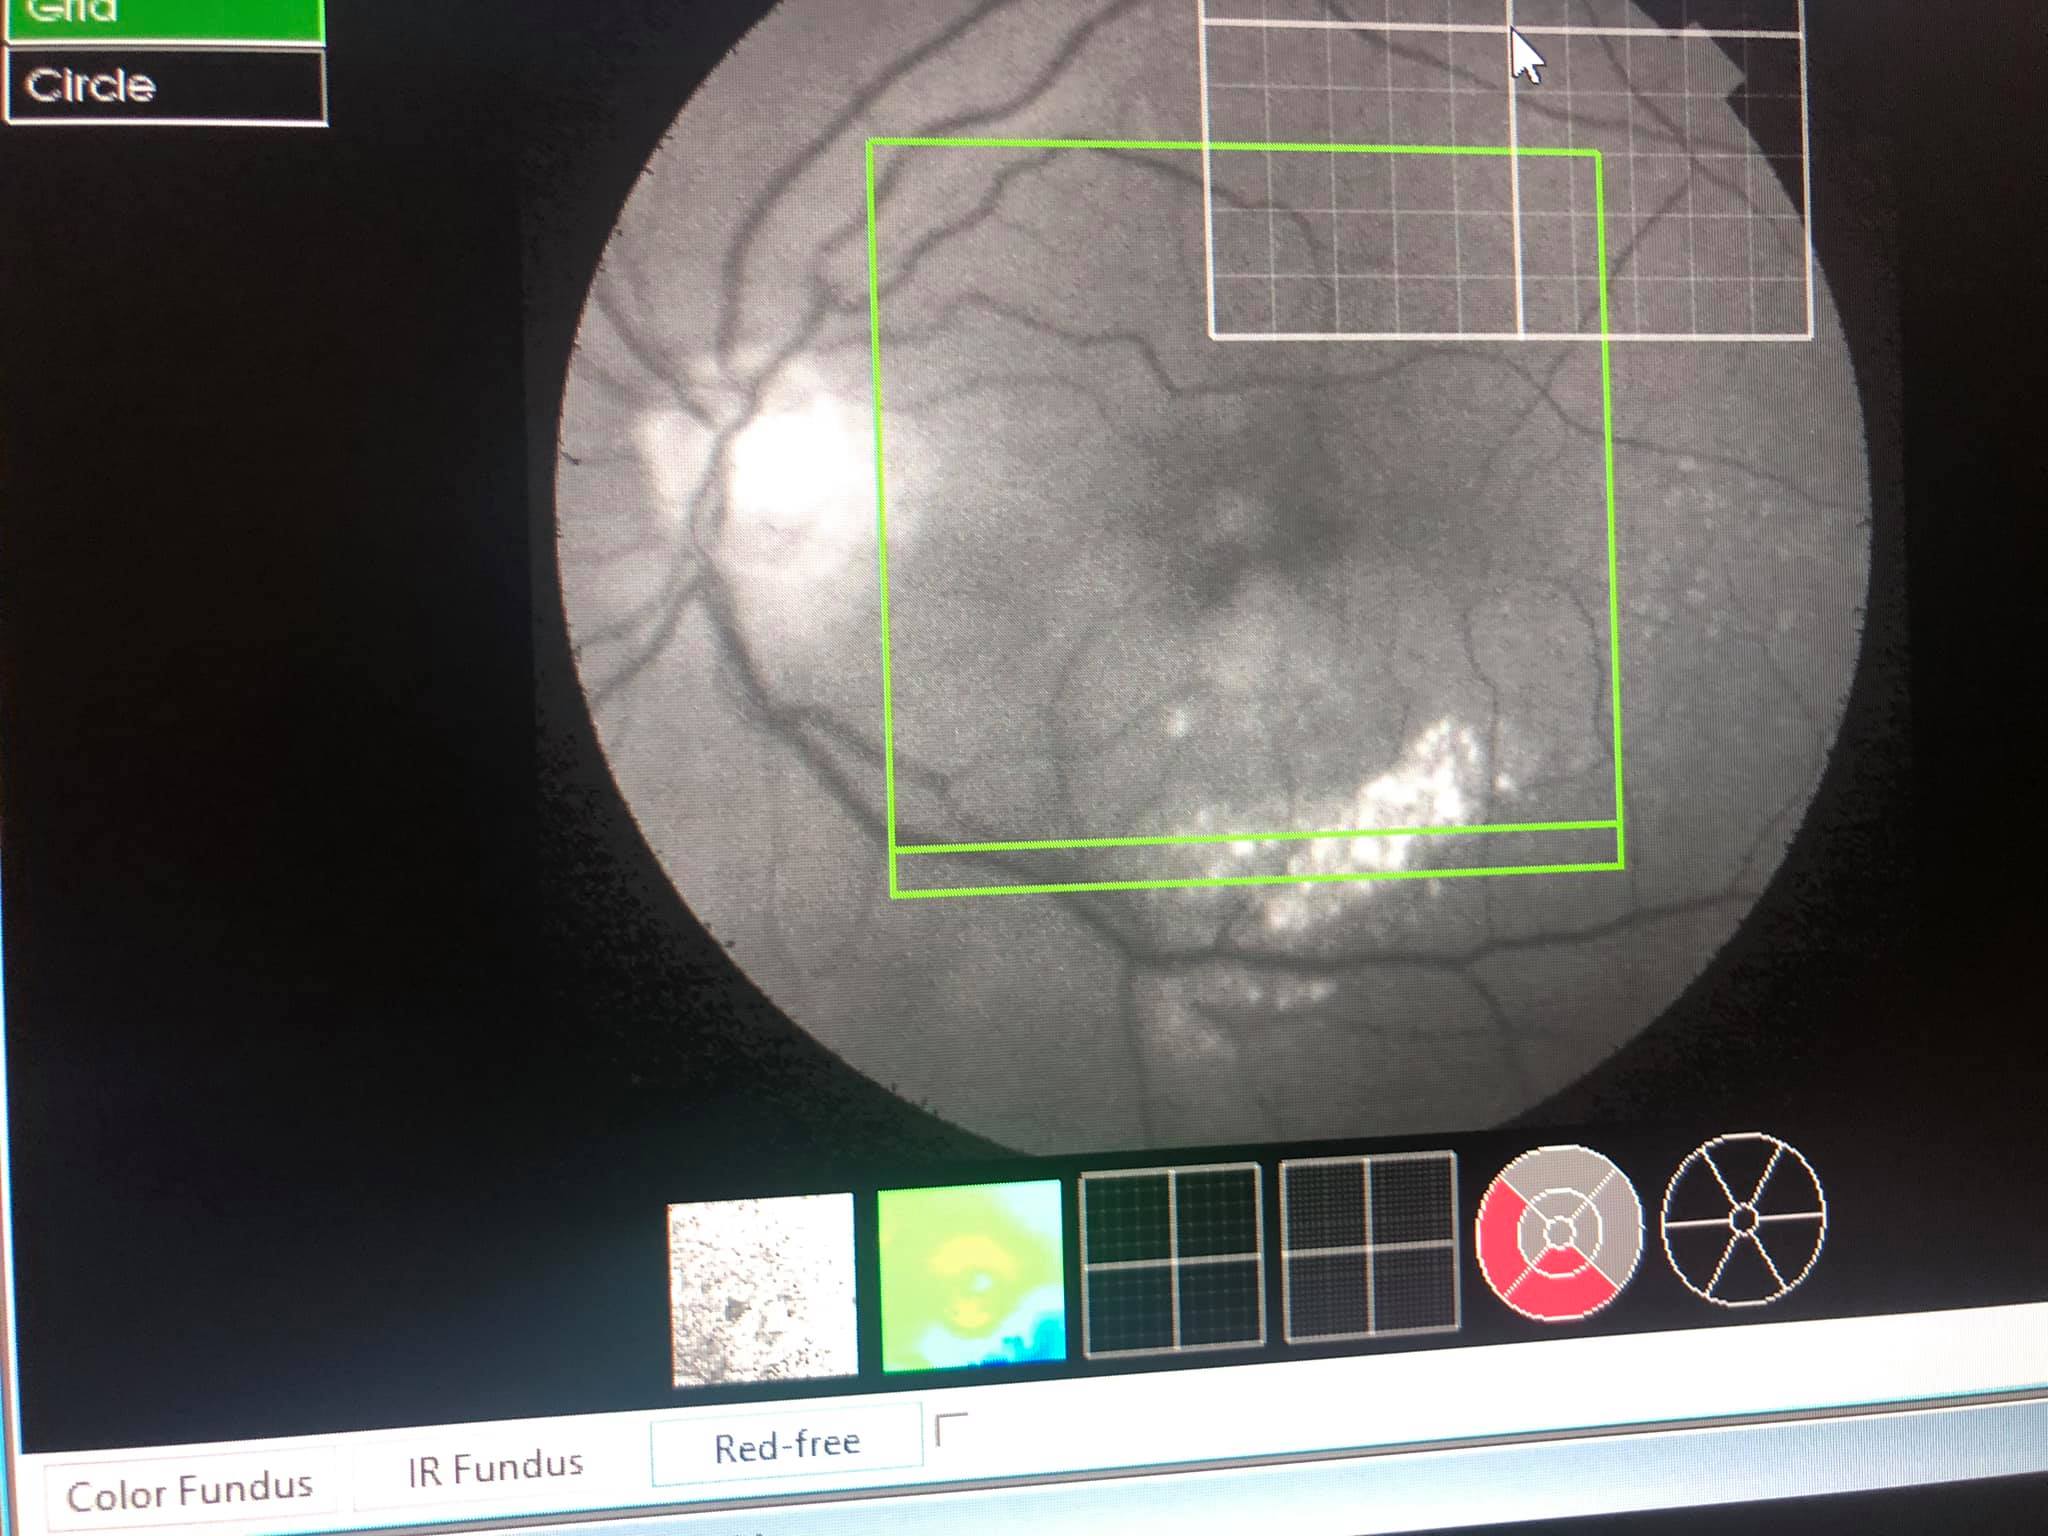

În diagnosticarea afecțiunilor retiniene, examenul fundului de ochi este esențial, dar adesea insuficient; pentru a vizualiza detaliile de structură inframicroscopice e nevoie de investigații imagistice: fotografia color retiniană, tomografia retiniană (OCT), angiofluorografia cu substanță de contrast sau tomografică (angioOCT).

Acestea sunt obligatorii în luarea deciziei terapeutice și în urmărirea evoluției în afecțiuni precum: retinopatia diabetică, degenerescența maculară, cu diversele ei forme, inclusiv membrane epi-retiniene, gaură maculară, edem macular de diverse etiologii și multe altele.

Din păcate, frecvent se întâmplă ca fundul de ochi să nu poată fi vizualizat, nici clinic, nici tomografic, din cauza unor opacități avansate la nivelul polului anterior (cataractă avansată sau leucoame corneene semnificative); în aceste situații, ecografia de pol posterior poate să ne dea o idee despre starea fundului de ochi, fără a fi, însă, capabilă să ne dea detalii despre anumite afecțiuni maculare. În schimb, ecografia oculară e esențială în diagnosticarea unor afecțiuni din periferia retinei, unde examenul clinic și tomografic ajung mai greu și ale unor boli precum dezlipirea de retină, retinoschizis-ul, decolarea de coroidă, prezența de corpi străini intraoculari, prezența sângelui în cavitatea vitreeană, tumori oculare, decolări maculare severe sau afecțiuni de nerv optic (drusen, excavații mari patologice, etc).